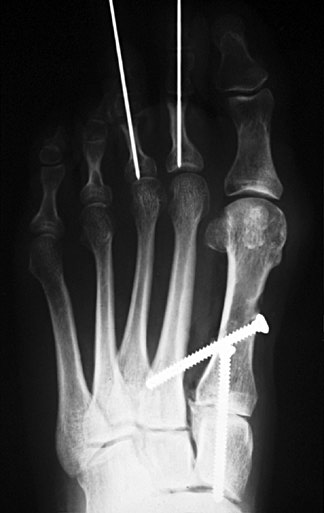

PostOp:

Same patient status post Lapidus procedure. With osteotomy of the 1st metatarsal, the 1st metatarsal head has been realigned in a more lateral and plantar location over the sesamoids. The 1st tarsometatarsal joint has been fused. Kirschner wires are seen in the 2nd and 3rd toes after osteotomy for clawtoe deformities.

Broken:

Broken screw following Lapidus procedure. Cancellous screws, especially the thinner ones, usually break at the junction of the shank and the threaded portion. Therefore, this probably represents at least a delayed union if not a nonunion. However, if correct position is maintained, as in this case, and the surgical site is painless, it may be considered a satisfactory result.